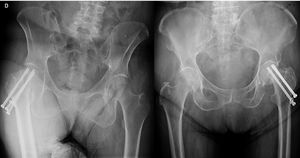

For patients in the CT group, K-wires were placed under fluoroscopic guidance, forming an inverted triangle. Once properly positioned, three cannulated, partially threaded screws were inserted following the direction of the wires to fix the fracture (Fig. 3).